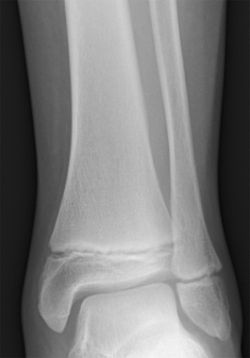

Radiogram of distal tibia (left) and fibula (right) showing two epiphyseal plates.